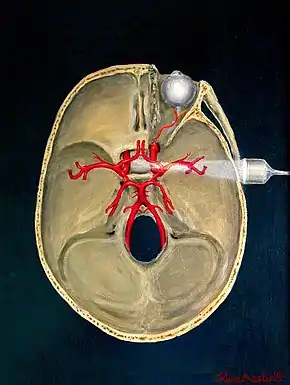

Transcranial Doppler (TCD) and transcranial colour Doppler (TCCD) measure the velocity of blood flow through the brain's blood vessels transcranially (through the cranium). These modes of medical imaging conduct a spectral analysis of the acoustic signals they receive and can therefore be classified as methods of active acoustocerebrography. They are used as tests to help diagnose emboli, stenosis, vasospasm from a subarachnoid hemorrhage (bleeding from a ruptured aneurysm), and other problems. These relatively quick and inexpensive tests are growing in popularity. The tests are effective for detecting sickle cell disease, ischemic cerebrovascular disease, subarachnoid hemorrhage, arteriovenous malformations, and cerebral circulatory arrest. The tests are possibly useful for perioperative monitoring and meningeal infection.[7] The equipment used for these tests is becoming increasingly portable, making it possible for a clinician to travel to a hospital, to a doctor's office, or to a nursing home for both inpatient and outpatient studies. The tests are often used in conjunction with other tests such as MRI, MRA, carotid duplex ultrasound and CT scans. The tests are also used for research in cognitive neuroscience.